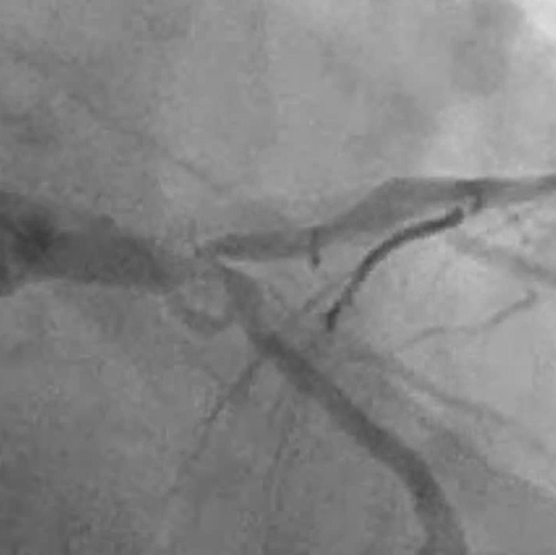

Balon ve/veya stent tedavisi, koroner anjiyografi sonrasında saptanan, kalbi besleyen atar damarlardaki kritik daralma ya da tam tıkanmaların tedavisinde kullanılan yöntemdir.

Balon ve/veya stent tedavisi koroner anjiyografi gibi anjiyo laboratuvarında hasta uyutulmadan, kasık veya el bileğinden giriş yerine lokal anestezi uygulandıktan sonra yapılır. İşlem süresi hastanın kliniğine göre değişmektedir. İşlem bitiminde hasta doktorunun önerisine göre uygun servise alınır. Koroner balon anjiyoplasti özel tasarlanmış malzemeler kullanılarak yapılır. Önce girişim yerine yerleştirilmiş kılıf vasıtasıyla kateter yerleştirilir bu kateterin içinden ilerletilen çok ince kılavuz telle damar darlık bölgesinden geçirilir. Bu kılavuz tel üzerinden balon kaydırılarak hasta bölgeye ulaştırılır. Daha sonra bu balon dışarıdan opak özelliği olan sıvı verilerek şişirilir ve darlığın açılması sağlanır. Sonrasında yapılan kontrolde açılmanın yeterli olduğunu tespit edilmesiyle işlem sonlandırılır. Düzgün açılma temin etmek nadirdir. Ayrıca ileride tekrar daralma riskini azaltmak için stentler hastaların büyük bir kısmında tercih edilmektedir. Başta, sadece çıplak, özel, paslanmaz nitelikteki metalden oluşan stentler kullanılmaktayken, günümüzde teknolojik ilerlemeye de bağlı olarak ilaç salınımlı nitelikte yeni ve farklı stentler de kullanılmaktadır. Hangi durumda hangi stentin kullanılacağına doktorun hasta ile konuşarak karar vermesi, doğru tedavi için tercih edilmesi gereken bir yoldur. Balon ve/veya stent işlemi, hastanın bir gün hastanede yatışını gerektiren bir uygulamadır. Hasta; doktor uygun gördüğü takdirde taburcu edilir. Taburcu olduktan sonra size reçete edilen ilaçları mutlaka düzenli kullanın! 2 gün ev, 15 gün iş istirahatı ile birlikte, 15 gün boyunca stresli ortamlardan, cinsel ilişkiden uzak durması çok önemlidir. Hastanın istirahat sonrası uçak yolculuğu ve uzun kara yolculuğuna çıkabilmesi de, doktorunun önerisine göre belirlenmektedir.